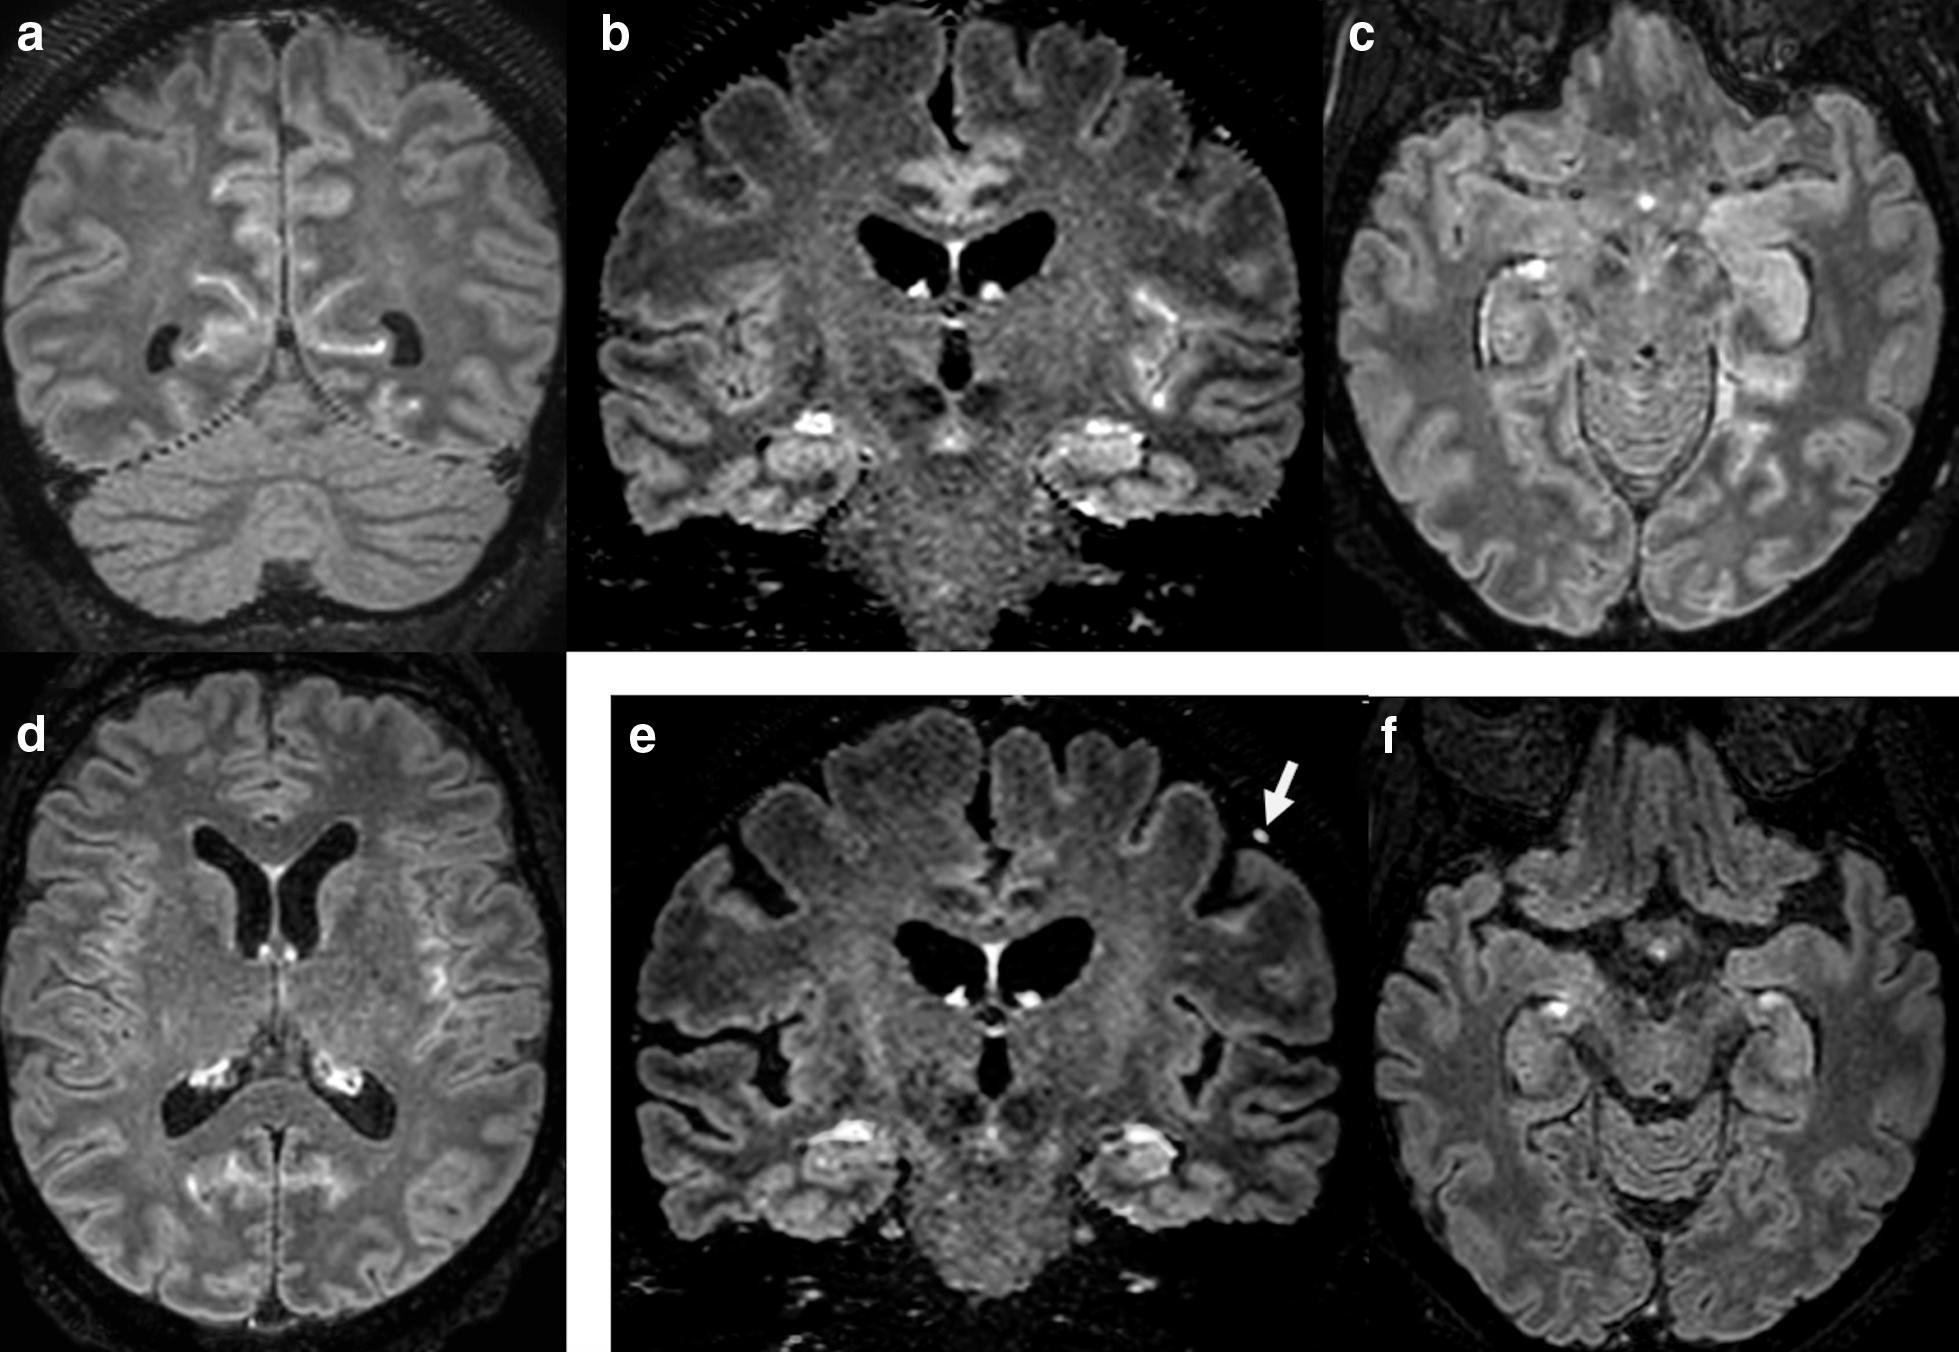

SARS-CoV-2-associated encephalitis: arguments for a post-infectious mechanism.

Picod Adrien, Dinkelacker Vera, Savatovsky Julien, Trouiller Pierre, Guéguen Antoine, Engrand Nicolas

Crit Care. 2020 Nov 23;24(1):658. doi: 10.1186/s13054-020-03389-1.